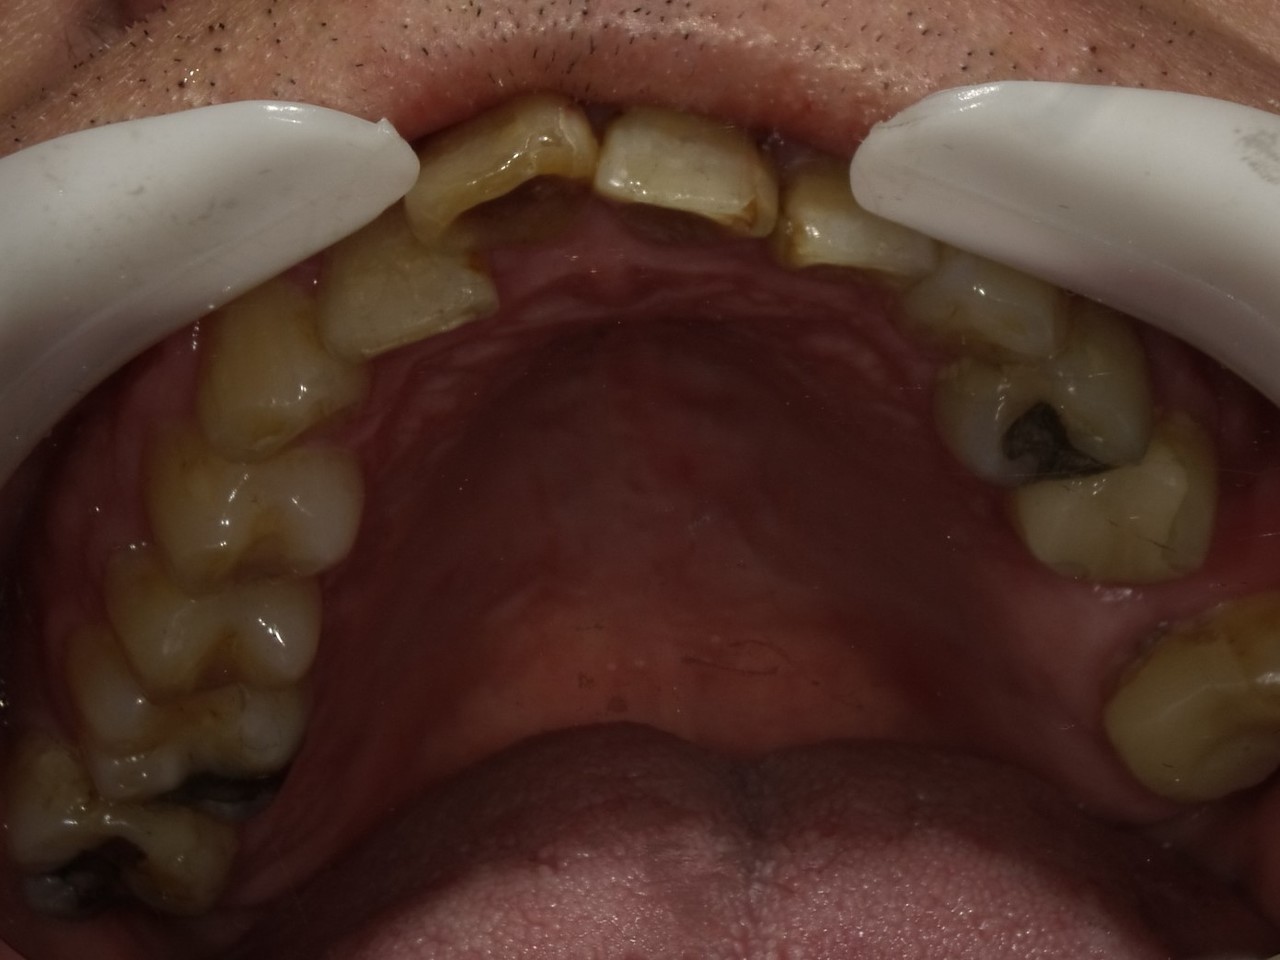

5.左上4番のインプラント抜歯即時埋入、左上6番の上顎既存骨1から2mmのグラフトレスサイナスリフト、左下56の大幅な骨欠損により、下顎神経の損傷を回避するために、ショートインプラントを使用し、左下56にインプラントを埋入し、最終補綴物は、左上456の3ユニットのジルコニアブリッジし、左下56は、ジルコニアの連結冠を装着したケース

Before

枚方市のインプラントの症例

After

M・I 様 女性 70代

症状としては、左下56は、歯周病で欠損したと考えられるが、かなりの骨欠損をともなっていた。左上456に関しては、動揺が大きく、炎症が起き、排膿、および、歯性上顎洞炎を起こしていた。

治療法としては、動揺がひどくなってきて、炎症の症状もあったため、左上56の抜歯を希望。インプラント治療をその後、希望したため、左上4に関しては抜歯即時埋入。左上6に関しては、既存骨1から2mmでインプラント治療が厳しい状態であったが、グラフトレスサイナスリフトを行い、治療期間5か月はかかるということを説明して、インプラント埋入をおこないました。その後、2か月半後、大幅に骨が欠損している下顎56に対して、ショートインプラントを使用して、下顎神経の損傷を避けて、インプラント埋入を終えています。その後2か月後に光学印象で印象を行い、上顎刺億456歯、3ユニットのジルコニアブリッジを装着。下顎左側56に関しては、骨欠損が大きいため、歯冠長がだいぶ長くなるため、ジルコニアの連結冠を装着して治療を終えた。

治療結果は、上顎6に関しては、既存骨が少なく、厳しい治療ではありましたが、5か月で治療を終え、患者様の負担を最小限に抑えるができたと考えます。(従来のサイナスリフトでは、このようなケースでは1年以上、1年程度の治療期間がかかるか、治療が不可能と言われるケースだと考えます。)また、下顎は骨欠損が大きく、下歯槽管のリスクが起きることが考えられますが、ショートインプラントを使用することで安全に治療を行うことができました。

治療の期間・回数:治療期間5か月(上顎456 3ピースブリッジの治療は5か月(上顎既存骨が2mm程度しかなく、骨結合に時間がかかるケースであったために、5か月の治療期間が必要であった。)(左下56に関しては2か月半で治療を終えています。)治療回数は、13回。

治療の価格:1,474,000円(税込)

治療費の内訳:左上46および左下56のインプラント基本料(フィックスチャー及び手術費用、投薬費用、レントゲン費用、インプラント上部費用(アバットメントおよびジルコニアクラウンの費用用)330000円(税込み)×4本分 1320000円(税込)。左上5ジルコニアポンテック費用88000円(税込)。オプション費用、左上4抜歯即時埋入加算(人工骨費用を含む)+グラフトレスサイナスリフト費用 33000円(税込)、左上6グラフトレスサイナスリフト費用 33000円(税込)

治療のリスクや副作用:手術後に、痛みや腫れ、出血、合併症などを引き起こす可能性があります。噛む感覚がご自身の歯と異なる場合があります。見た目がご自身の歯と異なる場合があります。手術後にメインテナンスを継続しないと、インプラントが抜け落ちる可能性があります。